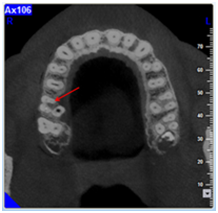

The treatment procedure consisted on the removal of the crown with the aid of a crown removal kit; ultrasonic tips were used for the removal of the metallic post, and the search for the entrance of the second mesial canal was conducted with the use of binoculars. While searching for the MB2 a perforation in the pulp chamber floor was performed. Decision was made to obturate the perforation with MTA and to postpone the session until a CBCT is done. While studying the CBCT, the cuts in the three planes (axial, sagittal and frontal cuts) showed a clearly not obturated canal in the mesial root in direct relation with the lesion (Figure 3). A new search for the MB2 entrance was conducted and finally the MB2 entrance is found. Endodontic therapy was done and two separated mesiobuccal canals where completely cleaned and obturated. A peri-apical radiograph was done five month later showing the complete cicatrisation of the lesion (Figure 4).

Figure 3 CBCT exam; the axial cuts show the entrance of the MB2, the sagittal and frontal cuts show an entire MB2 canal with the radiolucency attached to its apical part.